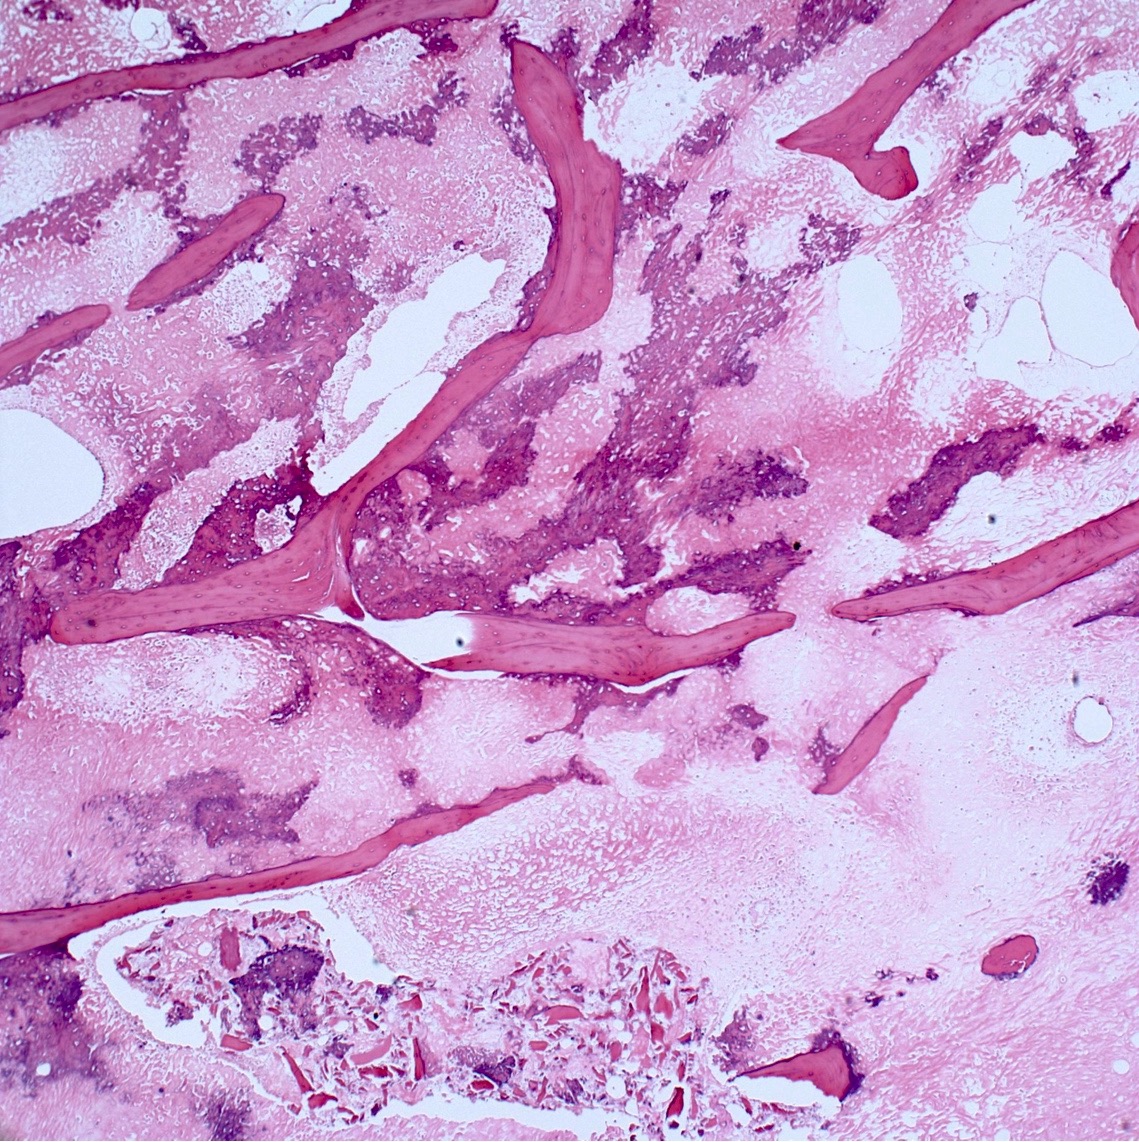

- Parosteal osteosarcoma:

- Invasion: tumor invades soft tissue; 25% invade bone (cortex / medullary)

- Neoplastic cells: fibroblast-like spindle cells (minimal atypia); between bony trabeculae (may be hypocellular)

- Scattered mitoses may be seen

- Neoplastic bone: parallel bony trabeculae (osteoblastic rimming may be present)

- Cartilage (present in ~50% of cases):

- Nodules within lesion (hypercellular)

- Cartilage cap: partially overlays tumor (moderate cellularity, chondrocytes are not arranged in columns, mild to moderate atypia)

- Dedifferentiation (15 - 25% of cases): abrupt transition to high grade sarcoma

- High grade osteosarcoma

- High grade undifferentiated pleomorphic sarcoma

- Fibrosarcoma

- Most common in recurrent tumors but may be seen in the primary tumor

Microscopic (histologic) images

Contributed by Jesse Hart, D.O., Borislav A. Alexiev, M.D. and AFIP